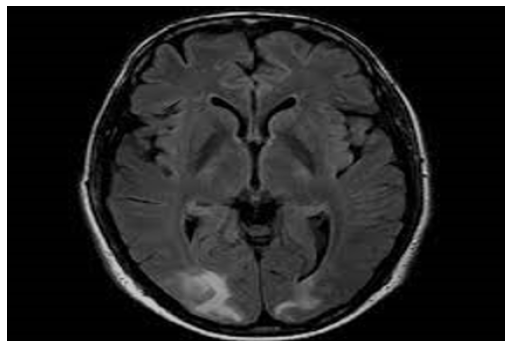

A 46-year-old male presented to an outside facility with depressed mental status, and hemoglobin of 3.1g/dL. The patient had a history of chronic flaccid paralysis secondary to Miller-Fisher variant GBS with tracheostomy and gastric tube dependence, seizures, deep venous thrombosis, and remote history of injection drug use. Other notable labs on initial presentation included: serum sodium of 160mmol/L, creatinine of 1.49mg/dL, calcium of 12.1mg/dL, and white blood cell count (WBC) of 17.1*109/L. The patient was normotensive to hypotensive throughout his stay in the outside facility and chest x-ray showed extensive bilateral patchy infiltrates. Two weeks prior to presentation, a computed tomography angiogram (CTA) of the chest showed diffuse consolidative changes throughout the lungs, a small pleural effusion, no pulmonary embolism. Per the outside facility report, and as was later corroborated with family, the patient was alert and oriented x3 at baseline and paralyzed from below the neck. Prior to transfer, the patient was transfused two units of packed red blood cells with relative stabilization of his anemia and mechanically ventilated via tracheostomy due to acute hypoxic respiratory failure. Brain imaging, including CTs and MRIs, showed confluent parietooccipital white matter hypodensity compatible with posterior reversible encephalopathy syndrome (Figure 1) [1-4]. Neurology was consulted upon arrival to our facility. Throughout the patient’s admission, his total serum calcium was persistently elevated and ionized calcium ranged 1.49 to 1.75mmol/L. Treatment with intravenous (IV) fluids, bisphosphonates and denosumab were required to correct patient’s hypercalcemia into the high normal range, but there was no noted change in mental status. During the patient’s hospital course, his renal function improved with intravenous fluid resuscitation. Given that the patient was normotensive to hypotensive, acute kidney injury resolved with fluids, and cytotoxic agents were excluded as potential triggers for PRES, it was determined that the patient’s persistent hypercalcemia was the most likely cause of his PRES syndrome. Despite aggressive medical interventions, the patient’s mental status did not improve and per family discussions, the patient was admitted to inpatient hospice for comfort measures only.